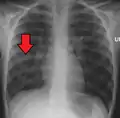

A chest radiograph is frequently used in diagnosis.[23] In people with mild disease, imaging is needed only in those with potential complications, those not having improved with treatment, or those in which the cause is uncertain.[23][67] If a person is sufficiently sick to require hospitalization, a chest radiograph is recommended.[67] Findings do not always match the severity of disease and do not reliably separate between bacterial and viral infection.[23]

X-ray presentations of pneumonia may be classified as lobar pneumonia, bronchopneumonia, lobular pneumonia, and interstitial pneumonia.[73] Bacterial, community-acquired pneumonia classically show lung consolidation of one lung segmental lobe, which is known as lobar pneumonia.[41] However, findings may vary, and other patterns are common in other types of pneumonia.[41] Aspiration pneumonia may present with bilateral opacities primarily in the bases of the lungs and on the right side.[41] Radiographs of viral pneumonia may appear normal, appear hyper-inflated, have bilateral patchy areas, or present similar to bacterial pneumonia with lobar consolidation.[41] Radiologic findings may not be present in the early stages of the disease, especially in the presence of dehydration, or may be difficult to interpret in the obese or those with a history of lung disease.[24] Complications such as pleural effusion may also be found on chest radiographs. Laterolateral chest radiographs can increase the diagnostic accuracy of lung consolidation and pleural effusion.[40]